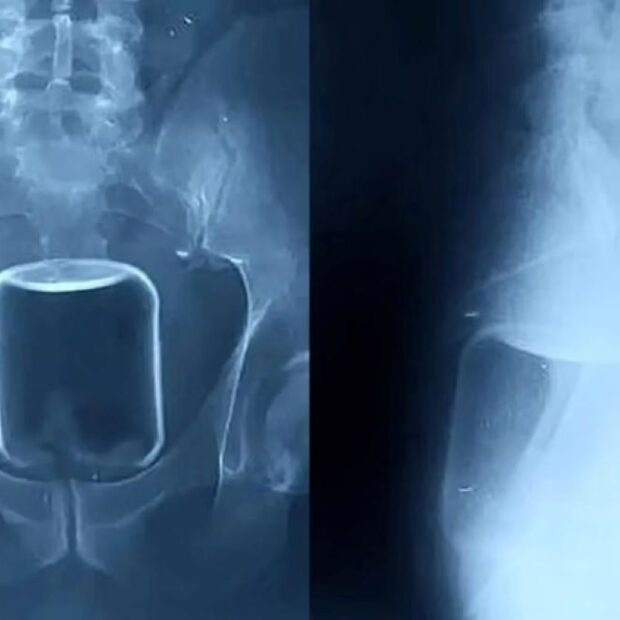

Imagens de raio-X divulgadas pelo hospital mostram um copo de vidro preso na parte superior do reto, avançando em direção ao intestino. Além do copo, os médicos também removeram um preservativo e lubrificante, que provavelmente foram utilizados durante a relação sexual.